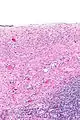

Serous cystadenomas are diagnosed by histomorphologic examination, by pathologists. Grossly, they are, usually, small unilocular cysts that contain clear, straw-coloured fluid. However, they may sometimes be multilocular. Microscopically, the cyst lining consists of a simple epithelium, whose cells may be either:[3]

- be columnar and tall and contain cilia, resembling normal tubal epithelium

- be cuboidal and have no cilia, resembling ovarian surface epithelium